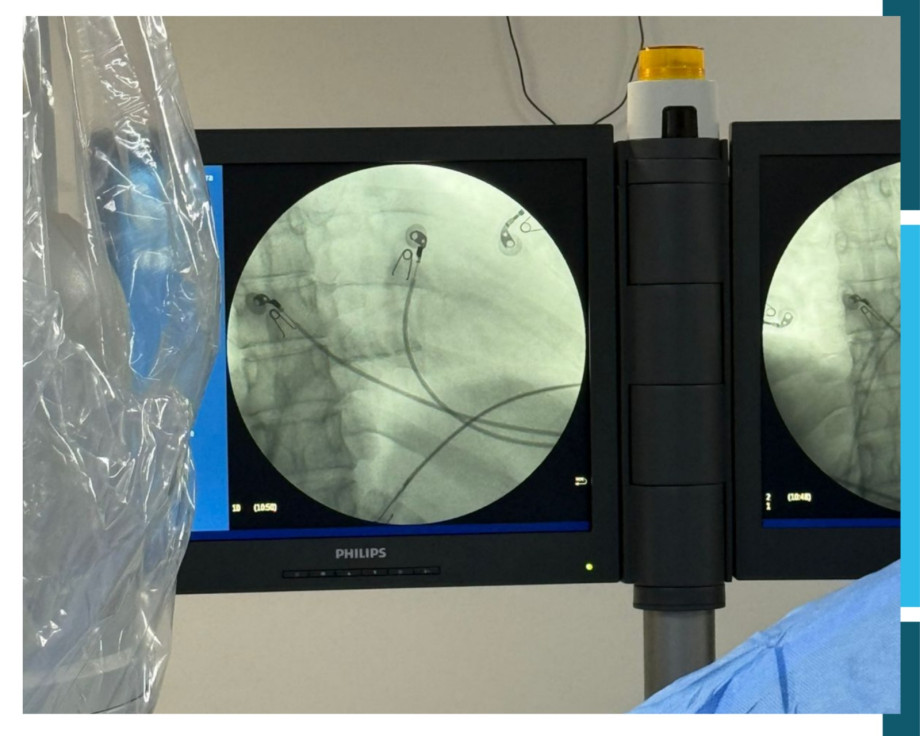

O Hospital Universitário São Francisco de Paula, HUSFP, marcou um importante avanço na saúde da região ao realizar seu primeiro estudo eletrofisiológico, procedimento fundamental para o diagnóstico e tratamento de arritmias cardíacas. O procedimento foi realizado no dia 31 de outubro pelo médico Dr. Thiago Camargo Moreira, especialista em eletrofisiologia.

O estudo eletrofisiológico é um exame avançado que investiga o funcionamento elétrico do coração. Por meio da introdução de cateteres finos nas veias ou artérias, o cardiologista consegue mapear os impulsos elétricos do coração, identificar ritmos anormais e determinar a origem de arritmias. Este diagnóstico preciso é essencial para orientar tratamentos adequados, que podem incluir desde ajustes de medicação até procedimentos de ablação, capazes de corrigir alterações no ritmo cardíaco.